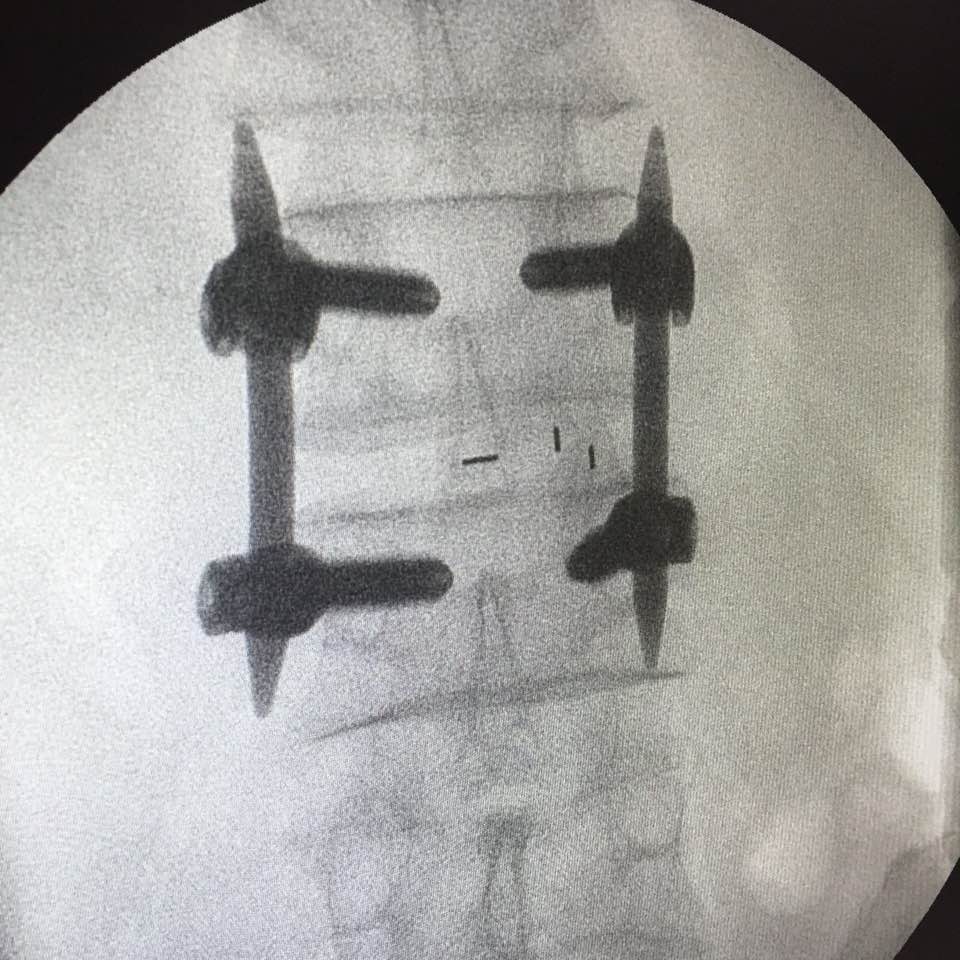

After the operation, he is now happily receiving the help of the lower back screws!